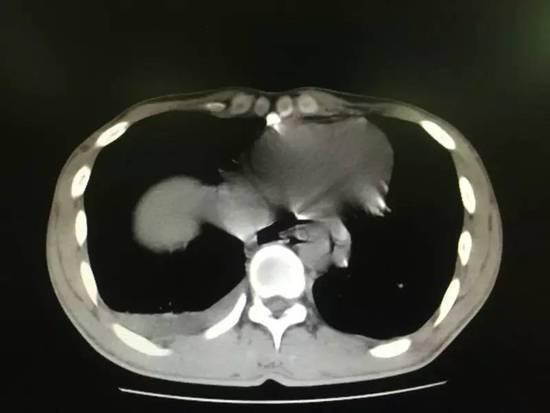

小伙聚餐喝二两白酒 吐得食道破裂伤口达8厘米

他因酒后呕吐小伙聚餐喝二两白酒 吐得食道破